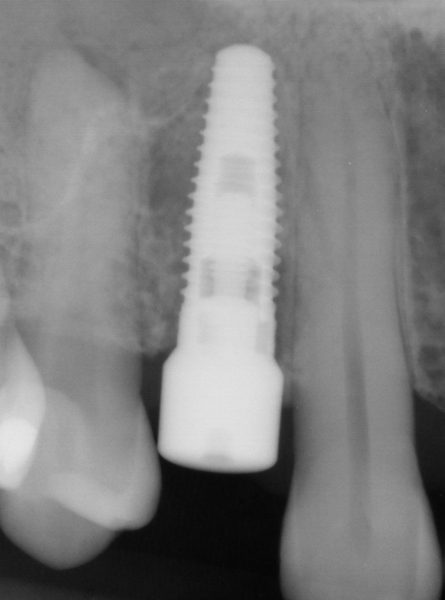

Screw-retained provisional restorations allow the creation of a seamless and cement-free transition from the head of the implant to the free gingival margin. This is critical during use in immediate load cases where wound healing will be occurring in contact with the abutment. The screw-retained approach also allows for easy access and manipulation of the emergence profile should the need arise. Three components are needed to fabricate a screw-retained provisional restoration: titanium abutment, clinical screw, and provisional tooth shell (acrylic, composite, polycarbonate, etc.) (Figure 7).

Abutment selection for the provisional restoration must meet three key criteria: biocompatibility, high strength, and narrow. Though variation exists between systems, a narrow-diameter titanium abutment is generally available and easily meets the above criteria. When implemented in immediate load cases, strength of the abutment is critical to avoid having to manipulate components at the head of the implant during the period of low implant stability. Some provisional abutments are designed with a flared collar at the interface that can be removed (Figure 8 and Figure 9) to enhance the potential soft-tissue volume during healing.18 The length of the abutment will need to be shortened to fit within the tooth shell. Any adjustments to the abutment are to be done outside the mouth to avoid titanium debris in the wound and transfer of heat and vibration to the implant. It is esthetically beneficial to opaque the surface of the abutment with a low-viscosity opaquing resin. This will help to minimize any graying of the provisional.